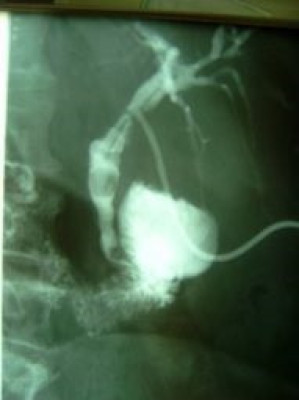

Litotripsia y extracción de cálculo de coledoco residual

Envíado por Dr. Carlos Miguel Zavaleta Consuegra